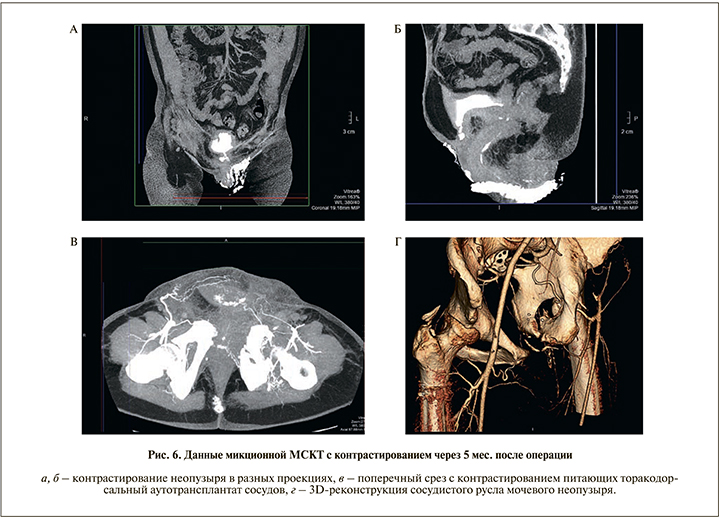

В послеоперационном периоде отмечено удовлетворительное дренирование нижних мочевых путей. При контрольной урографии выделительная функция почек была сохранена. Отток мочи осуществлен по мочеточниковым и уретральному катетеру, составив около 1500 мл/сут. Дважды производили замену мочеточниковых катетеров в связи с их плохим функционированием. Через 1,5 мес. сформированный мочевой пузырь удерживал около 250 мл мочи, самостоятельное мочеиспускание восстановлено полностью и осуществлялось как с помощью оставшейся части мочевого пузыря, так и путем напряжения передней брюшной стенки и/или надавливанием верхней конечностью в надлобковой области (рис. 6).